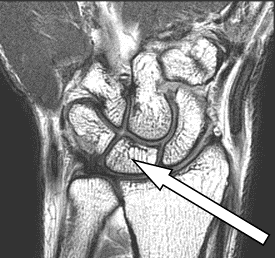

Na obrazie MR kręgosłupa lędźwiowego strzałką wskazano

Ilustracja do pytania 7

A. przepuklinę na poziomie L2-L3

B. osteofit na poziomie L2-L3

C. osteofit na poziomie L4-L5

D. przepuklinę na poziomie L4-L5